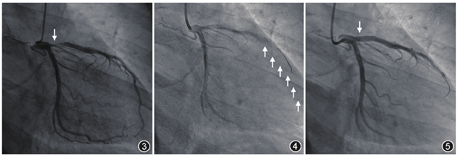

冠状动脉为右冠优势型,左主干粗大,发现左前降支开口99%局限偏心性狭窄(图3),前降支供血范围广,绕过心尖部,心肌梗死溶栓治疗(thrombolysis in myocardial infarction,TIMI)血流3级,但血流偏慢,其余冠状动脉未见动脉硬化及狭窄。为排除痉挛,立即给予硝酸甘油200 μg于冠状动脉内注射,可见左前降支血流较前改善,直径较前变粗,但开口部位狭窄仍为99%,考虑为固定性狭窄。

使用美敦力EBU 3.5指引导管及经皮冠状动脉腔内血管成形术(percutaneous transluminal coronary angioplasty,PTCA)球囊,球囊大小为2.5 mm×20.0 mm,以14 atm(1 atm=101.325 kPa)预扩张病变血管,然后采用3.0 mm×10.0 mm切割球囊以10 atm切割病变血管。因患者为ACS且斑块负荷重,血管直径粗,加之造影时血流偏慢,考虑该患者为无复流发生高危人群,故没有立即进行造影,而是先预防无复流的发生。因患者负荷双联抗血小板药物时间距离PCI时间较短,故冠状动脉内注射替罗非班10 ml,复查造影提示TIMI血流3级,拟植入4.0 mm×25.0 mm药物涂层支架,左前降支开口精确定位,释放压力14 atm,撤出球囊"冒烟",提示支架以远发生无复流(图4),立即给予腺苷200 μg于冠状动脉内注射,复查造影提示血流显著改善,TIMI血流3级,但支架近段膨胀不全,送入5.0 mm×10.0 mm半顺应性球囊扩张支架近段,扩张压力为16 atm。因球囊在高压下扩张,为预防无复流发生,冠状动脉内再次给予腺苷200 μg,前后位(anterior-posterior,AP ) 30°造影提示左前降支血流正常,但支架远段局部膨胀不良,送入4.0 mm×15.0 mm半顺应性球囊送以18 atm扩张,撤出球囊,在最终造影前为预防无复流,冠状动脉内先后给予硝酸甘油200 μg及腺苷200 μg,造影提示支架形态良好(图5),TIMI血流3级,结束手术,术中出血量约10 ml。